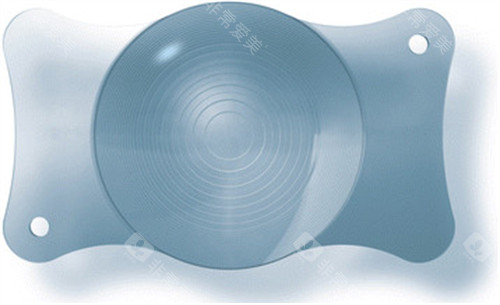

尤其在夜间驾驶时,患者可能因灯光周围出现光晕而难以判断路况。一位ICL晶体植入患者反映,术后夜间看车灯时出现明显光晕,需避免夜间出行。

过敏反应:材料兼容性的“隐形考验”

极少数患者对人工晶体材料(如亲水性丙烯酸酯)或术中使用的粘弹剂过敏,表现为眼部红肿、疼痛。

若未及时识别并更换晶体材料,可能引发慢性炎症。

手术决策需综合考量眼部条件、全身健康状况及个人需求。对于高度近视患者,若角膜厚度不足无法接受激光手术,ICL晶体植入仍是优选;对于白内障患者,人工晶体置换是改善视力的仅有途径。